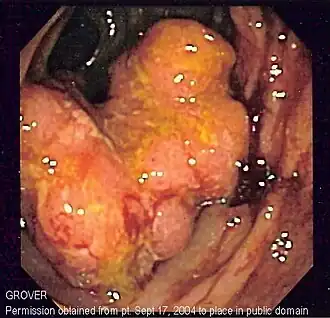

![]() Imagine endoscopică a cancerului colorectal | |